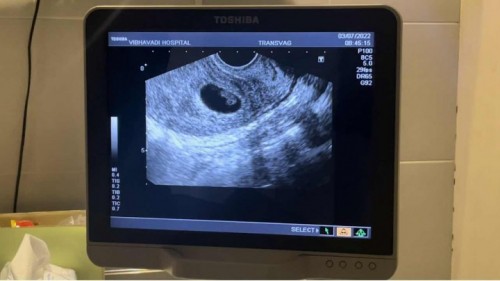

วันนี้ได้พบหมอ 11W+ แต่เจอข่าวร้าย น้องหัวใจหยุดเต้นแล้วค่ะ ตั้งแต่ช่วง 7W. พบหมอครั้งแรก 6W เจอตัวน้องหัวใจน้องเต้นดี แต่วันนี้ไม่มีอีกแล้วค่ะ 😢😢 . . ปล่อยมีน้องมา 2 ปีน้องเพิ่งมาค่ะ ถ้ารอมีอีกจะนานไหมคะ 🥹 แล้วนานไหมคะกว่าน้องจะขับออกมาเอง เผื่อแม่ๆมีประสบการณ์แชร์ได้นะคะ ลืมถามหมอด้วยค่ะ 🙏🏼